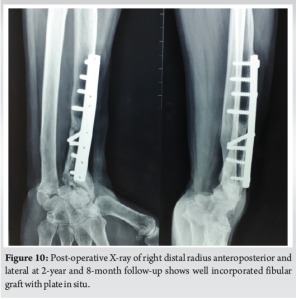

At 2 year and 8 months of follow-up, the patient had (Fig. 9) wrist palmar flexion of 30°, pronation of 70°, supination of 20°, dorsiflexion is NIL. The fibular graft was shorter in comparison to the length of ulna. Probably, if we had taken a longer fibular graft, range of movements may have been better as ulno-carpal impingement could have been avoided. X-ray showed that the fibular graft had well incorporated (Fig. 10).

A lower rate of recurrence has been noted after resection of the distal part of the radius in compared with curettage, especially when the tumor has the cortex or when there has been rapid enlargement of the lesion or a local recurrence. After resection, the defect has been reconstructed as an arthroplasty or an arthrodesis involving use of either vascularized or non-vascularized bone grafts from the tibia, the proximal part of the fibula, the iliac crest, or the distal part of ulna [5]. Although there are advantages to the use of vascularized bone grafts, non-vascularized bone graft was successfully employed in our patient. The advantages of vascularized graft may be less important in the distal radius, due to its relatively short length of resection and graft. Resection with wrist reconstruction by using autogenous proximal fibular grafting without fusion enables the patient to achieve some function at the wrist as compared to fusion. Wide local excision of tumor and reconstruction with ipsilateral proximal fibular autograft allows preservation of movements of the wrist. Patients can return to useful employment despite their functional limitations [6]. Hence, the study used wide excision and autogenous fibular graft as the treatment of choice. There are no signs of recurrence of the tumor till 3 years of follow-up. At 1 year of follow–up, some degree of osteolysis of fibular head was seen which is commonly noted in both free and vascularized proximal fibula autograft. This may be due to loss of vascularity of the fibular head. Our fibular graft was slightly short. The distal end of ulna was impinging on carpus because of which movements were probably restricted. Probably, if we had harvested a longer graft, range of movements of wrist may have been better.